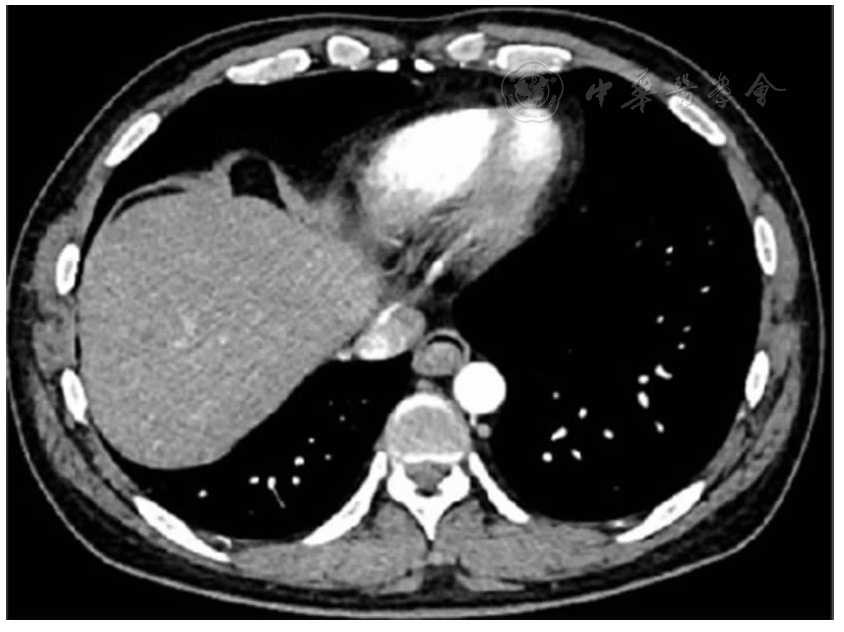

临床资料:患者男,40岁,因"发现食管下端占位性病变2月余"于2022年06月09日收入西安交通大学第二附属医院消化内科。患者自诉:2月前因胸闷气短于外院就诊,查冠脉CTA提示:左前降支近端阶段性轻度狭窄,胸部食管下段软组织密度影,考虑占位性病变。外院胃镜检查示食管隆起性病变(性质结合病理),病理活检诊断报告:(食管)病变组织被覆鳞状上皮,上皮增生,其下间质可见炎性细胞浸润。建议行超声胃镜检查。近期患者自觉反酸烧心,无吞咽障碍,无其他不适症状来我院就诊。入院后实验室检查血尿粪常规、凝血功能、肝肾功、电解质、男性肿瘤标志物全套无明显异常。2022年6月14日本院内镜检查提示:食管下段距门齿35 cm可见一大小约2.5 cm × 1.5 cm不规则隆起性病灶,表面光滑,局部发红,稍凹陷,向腔内生长(图1)。超声内镜(endoscopic ultrasonography,EUS)检查示:食管病变处扫描见黏膜深层及黏膜下层不均匀偏低回声占位,内部未见血流,局部与黏膜层粘连,黏膜下层未中断,固有肌层未见异常占位,壁外、纵隔内未见肿大淋巴结;病变最大截面大小约29.7 mm×12.9 mm。诊断:食管隆起性病变考虑黏膜深层及黏膜下层偏低回声占位(图2)。胸部增强CT示:食管下段管壁增厚并结节状凸向腔内,管腔呈偏心性狭窄,增强后管壁呈渐进性强化;诊断:食管下段肿瘤性病变待排(图3)。上腹部平扫及增强CT未见明显异常。无明显手术禁忌,2022年6月15日在气管插管全麻下行内镜下黏膜剥离术(endoscopic submucosal dissection,ESD),完整切除病灶(图4)。

图3 食管下段结节状占位性病变凸向管腔